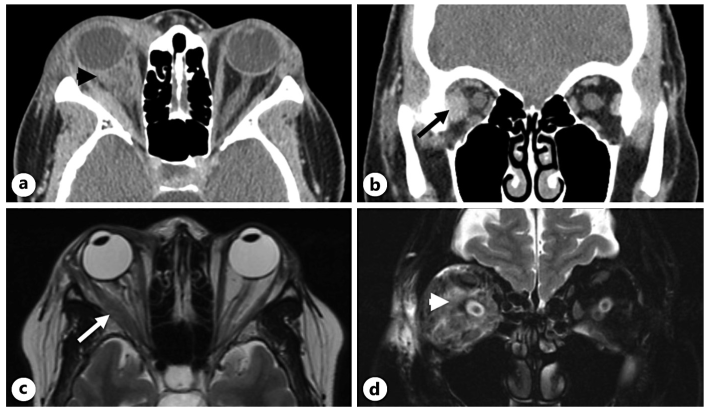

• 辅助检查:实验室检查显示红细胞沉降率(ESR)轻度升高(38 mm/h),血管紧张素转化酶(ACE)偏低,感染及自身免疫性疾病筛查均为阴性。影像学检查(眼眶 CT 及 MRI)显示:右侧眼眶脂肪条索影,眼外肌(尤其是外直肌)弥漫性肿大,但未见明确的肿块病灶(图 1)。

图1 (A, B)眼眶增强 CT:显示双侧眼球突出,右侧眶前肿胀及肌锥内脂肪条索影(黑箭头),外直肌肿大(黑长箭头),未见明确肿块;(C, D)T2 加权 MRI:显示右侧外直肌肿大(白长箭头)及肌锥内脂肪条索影(白箭头)。